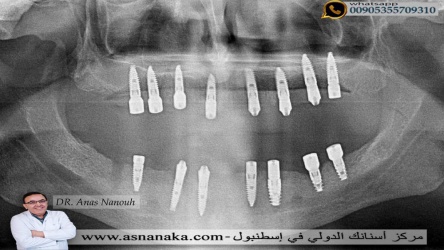

السؤال الذي يسأله دائما المراجعون لي من خلال رقمي على الواتساب هو ما هو العدد المناسب لزراعه الاسنان في كل فك في الواقع ان الحد الاعلى لزراعه الاسنان في كل فك تقريبا 10 زرعات ولكن زراعة 8 زرعات في كل فك رقم جيد وكافي بل وممتاز وفي هذه الحاله نعرض لكم عمليه زراعه اسنان بدون شق شراحي لمراجع من المغرب العربي زرعنا له زرعات المانيه من شركه ريتر ritter وقت تم زراعه ثمانية زرعات في الفك العلوي و 7 زرعات في الفك السفلي وقد تم تركيب تركيبات زيركون فوق الزراعات في الزياره الثانيه بعد اربعه اشهر وحصل على ابتسامه هوليود كما ستشاهدون في الصور اللاحقه

صوره شعاعيه لزراعات الاسنان وقت تم زراعه ثمانيه زراعه في الفك العلوي وسبع زراعات في السفلي